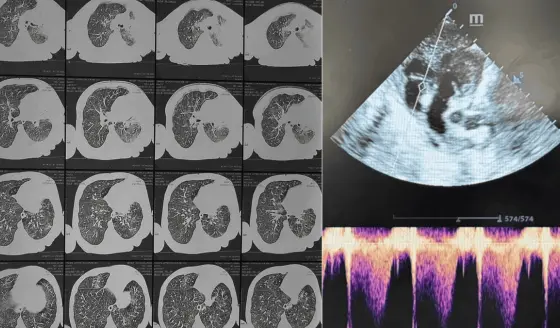

El abordaje de la incontinencia urinaria comienza con una evaluación clínica. La Dra. Azkarate explica que "son pruebas que permiten valorar cómo funciona la vejiga y la uretra, midiendo la presión, la capacidad y la fuerza del flujo urinario".

Estos estudios urodinámicos, combinados con una historia clínica detallada, permiten identificar el tipo específico de incontinencia y diseñar un plan de tratamiento personalizado. El diagnóstico diferencial es crucial, ya que existen varios tipos con características y abordajes distintos.